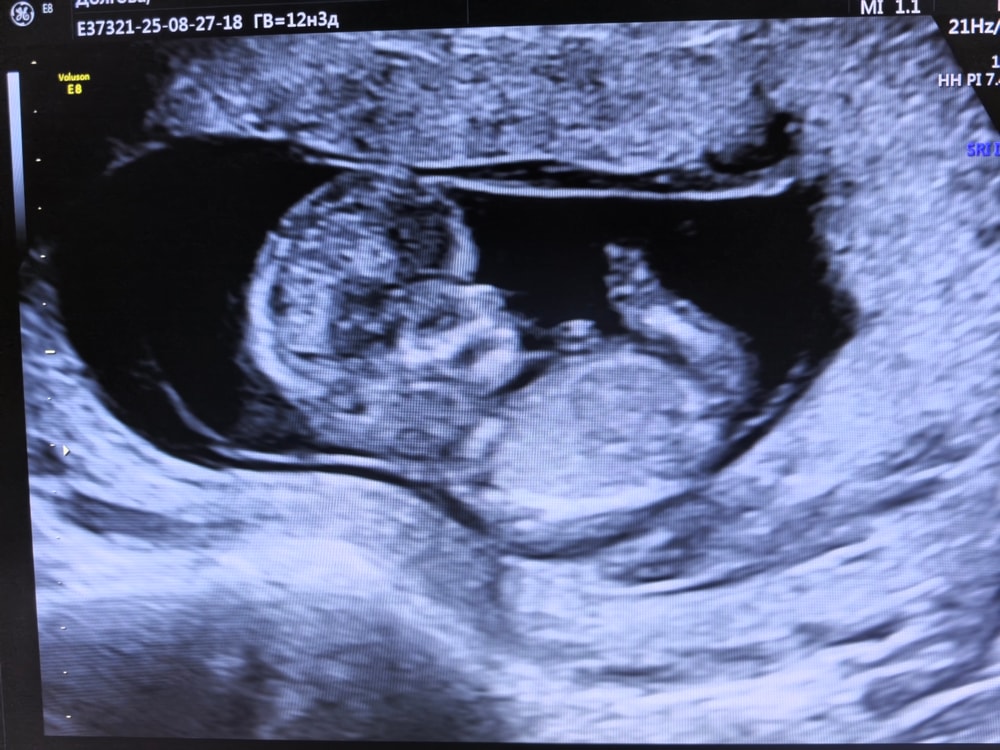

1 скрининг

Ну что, вот и первый скрининг позади

По овуляции я считаю срок 12,3, а малышочек на 12,4

66мм зайчик 💙

По узи без нареканий, по крови узнаю 10 сентября на приеме у гинеколога